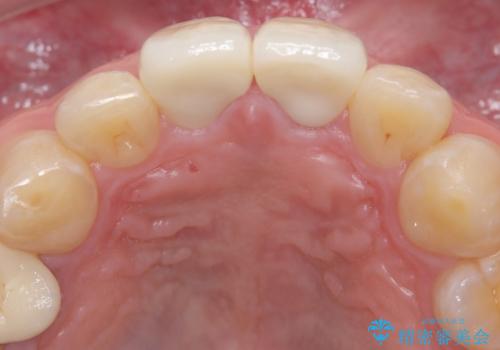

前歯の根のところに違和感がある|根尖性歯周炎|精密根管治療|オールセラミッククラウン|見た目も改善

- 前歯の違和感を主訴にご来院された患者様です。

根尖性歯周炎に罹患し根の先に膿が溜まっているのが原因でした。

精密根管治療後、オールセラミッククラウンで治療を行いました。

治療後、違和感は無くなりました。

治療後、違和感が無くなり、被せ物で歯の長さが揃い見た目も改善されとてもご満足していただけました。